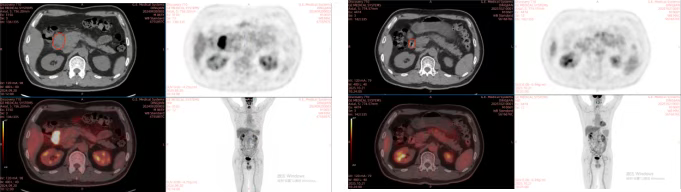

Case 2: Patient Ding with Malignant Tumor of the Duodenum

Brief Medical History: Patient Ding, male, 65 years old, Chief Complaint: Discovery of malignant tumor of the duodenum 3 weeks ago. On August 28, 2024, abdominal + pelvic CT at Xi'an Ninth Hospital suggested: Consider occupying lesion in the descending part of the duodenum (size approx. 5.3×4.1×4.6cm); scattered enlarged lymph nodes around the lesion and in the retroperitoneum (size approx. 1.8×1.9). Pathological results suggested: Malignant tumor of the duodenum. On September 18, 2024, ultrasound endoscopy-guided puncture biopsy at our hospital showed: (Descending part of duodenum) Malignant tumor, based on morphological changes and immunohistochemistry results, mostly considered ALK-positive anaplastic large cell lymphoma. Definitive diagnosis: Malignant tumor of the duodenum, ALK-positive anaplastic large cell lymphoma, IPI score 1 point, Lugano stage IIE, Ann Arbor stage IIE, TNM stage for gastrointestinal lymphoma (Paris classification) IIE; KPS score: 90. Carbon ion therapy began on 2024-09-30: PTV: 40Gy(RBE)/10Fx. One cycle of XELOX regimen systemic intravenous chemotherapy was administered on 2024-09-23, specific medication: Oxaliplatin (130mg/m²) 244mg ivgtt d1 + Capecitabine tablets (800mg/m²) 1.5g po Bid d1-14 Q3W. One cycle of CHP regimen systemic intravenous chemotherapy + Brentuximab Vedotin targeted therapy was administered on 2024-10-17, specific medication: Cyclophosphamide (750mg/m²) 1300mg ivgtt d1 + Doxorubicin (40mg/m²) 70mg ivgtt d1 + Prednisone 100mg po d1-5 Q3W + Brentuximab Vedotin (1.8mg/kg) 100mg ivgtt d1 Q3W.

2. Imaging Comparison

2024-09-20 2025-10-16